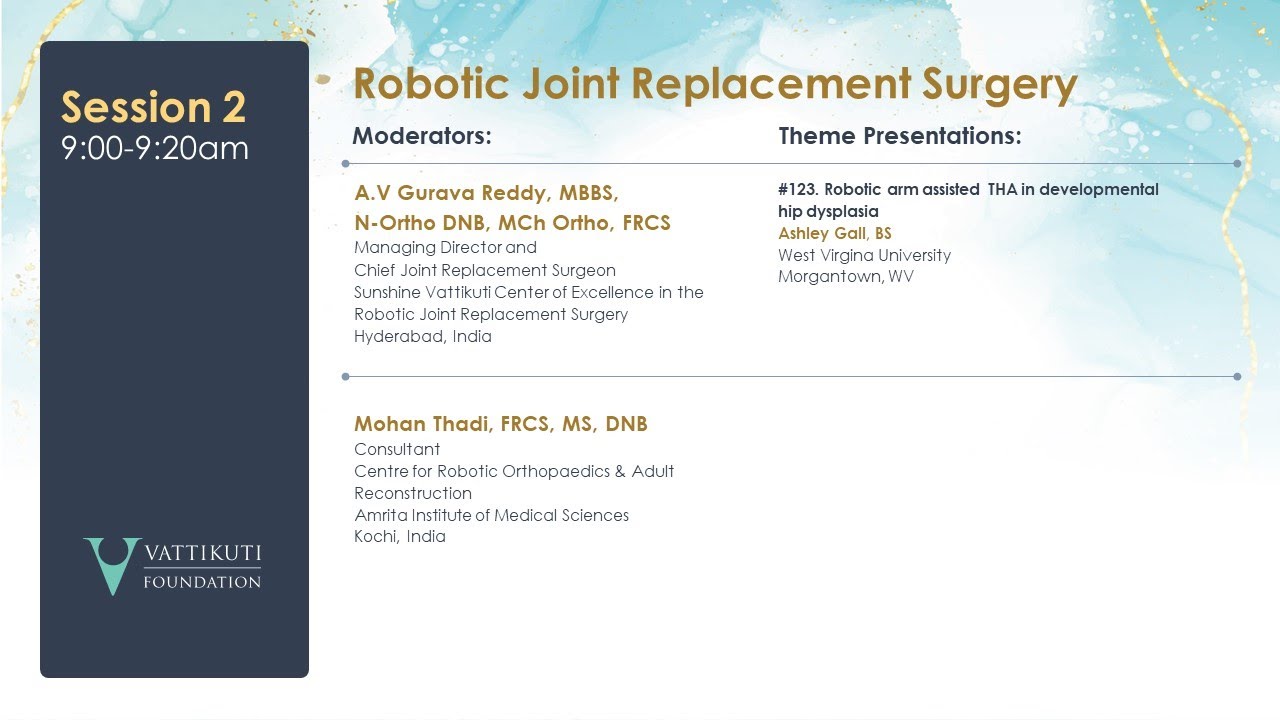

Robotic-Arm Assisted THA in Developmental Hip Dysplasia